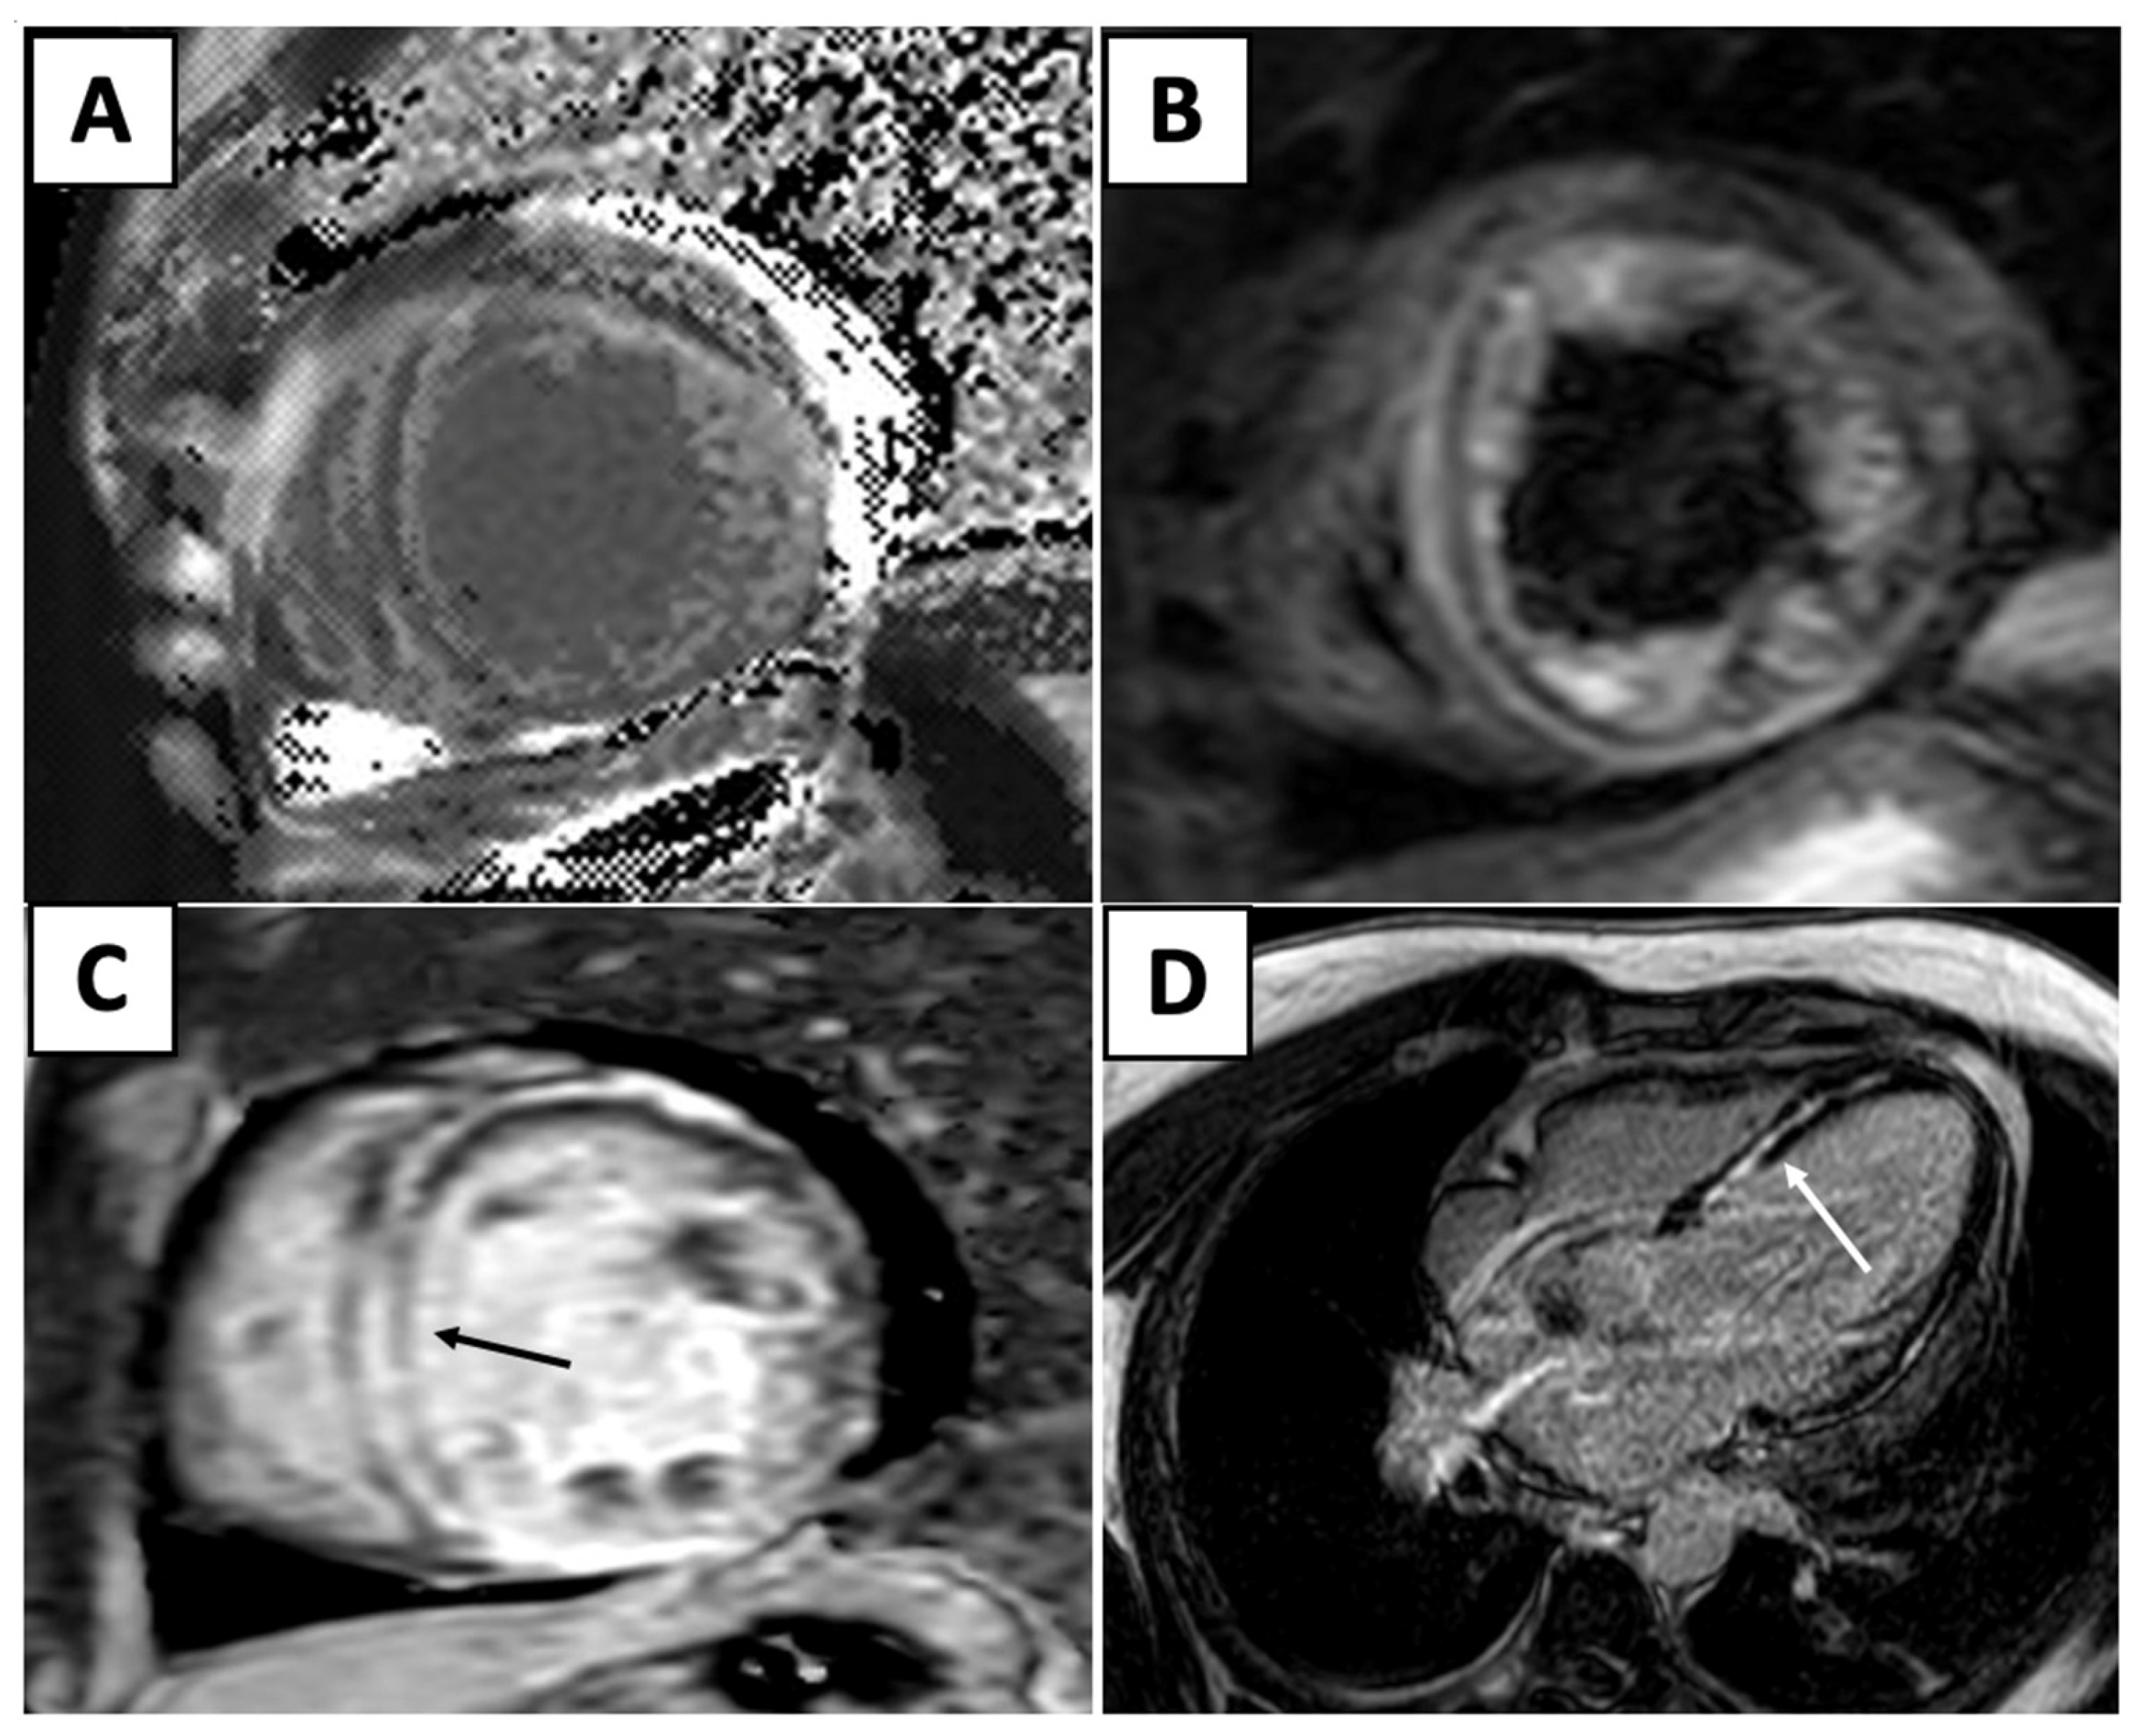

| Cardiac MRI | ![]() | Short-axis view reveal interventricular mid-myocardial LGE (black arrow). |